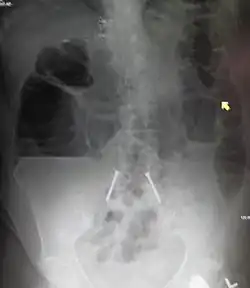

![]() | |

| Upright abdominal X-ray demonstrating a small bowel obstruction. Note multiple air fluid levels. | |

Radiological signs of bowel obstruction include bowel distension (small bowel loops dilated >3 cm) and the presence of multiple (more than 2) air-fluid levels on supine and erect abdominal radiographs.[16] Ultrasounds may be as useful as CT scanning to make the diagnosis.[17]